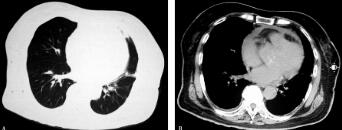

患者经抗感染治疗,病情好转,体温正常,血常规正常,D-二聚体1890μg/L,血沉38mm/h,C-反应蛋白15.6mg/L。2012年9月10日复查经胸壁心脏彩超提示赘生物较前减少。复查胸部CT提示左上叶斑片影较前(2012年6月20日和2012年8月15日)吸收(图3A肺窗、B纵隔窗)。经心外科会诊考虑病情好转,无心衰、感染扩散以及栓塞等并发症,故无手术指征,于2012年10月9日出院,定期门诊随诊。

图3

在本病例诊治过程中,尽管临床医师始终在进行CAP的鉴别诊断,例如,特殊病原体检查、寻找其他部位感染灶和非感染性发热的筛查,但误诊原因在于:对于发热+肺部阴影的患者,诊断“CAP”后,只要体温恢复正常,临床症状好转,即认为诊断明确,治疗有效;而忽视了胸部CT影像学吸收程度的随访。该患者因再次发热入院时(出院1个月余),胸部CT未见变化,说明该病例首次住院病情好转,是抗感染有效,仍不能反过来证明“CAP”的诊断,甚至似乎推翻“CAP”诊断;只有第三次复查胸部CT(3个月)发现原发病灶吸收,才能证实首次“CAP”诊断明确;8个月后(2013年2月20日)随诊复查胸部CT(图4A肺窗、B纵隔窗)提示左上叶病灶吸收,进一步明确“CAP”诊断。因此,社区获得性肺炎和亚急性感染性心内膜炎均诊断明确,引起反复发热的原因是亚急性感染性内膜炎。从该病例的诊治过程,我们进一步认识到“一元论”的观点是“双刃剑”,需要临床医师灵活运用。